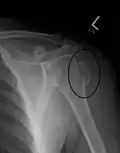

Proximal humerus fracture -